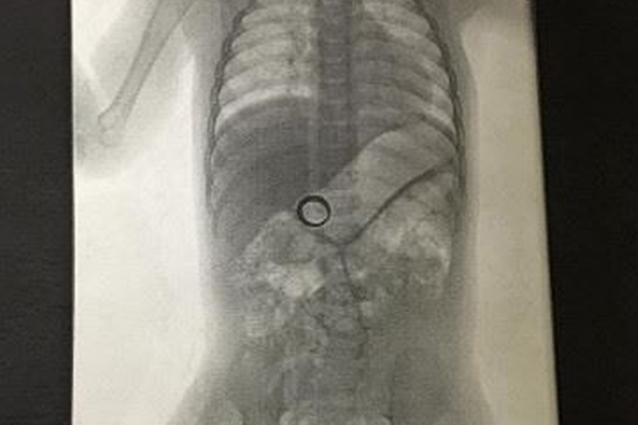

Così il padre decide di far fare al piccolo una bella lastra, e una volta svelato l’arcano, ha postato l’immagine su Reddit.

Morale: il bambino – di appena 14 mesi – era riuscito ad afferrare l’anello nuziale della madre e se l’era ingoiato. A quel punto i due, non hanno dovuto far altro che aspettare che il piccolo producesse il dovuto nel proprio pannolino… e setacciando con cura avrebbero ritrovato l’ambito attestato di eterno amore.